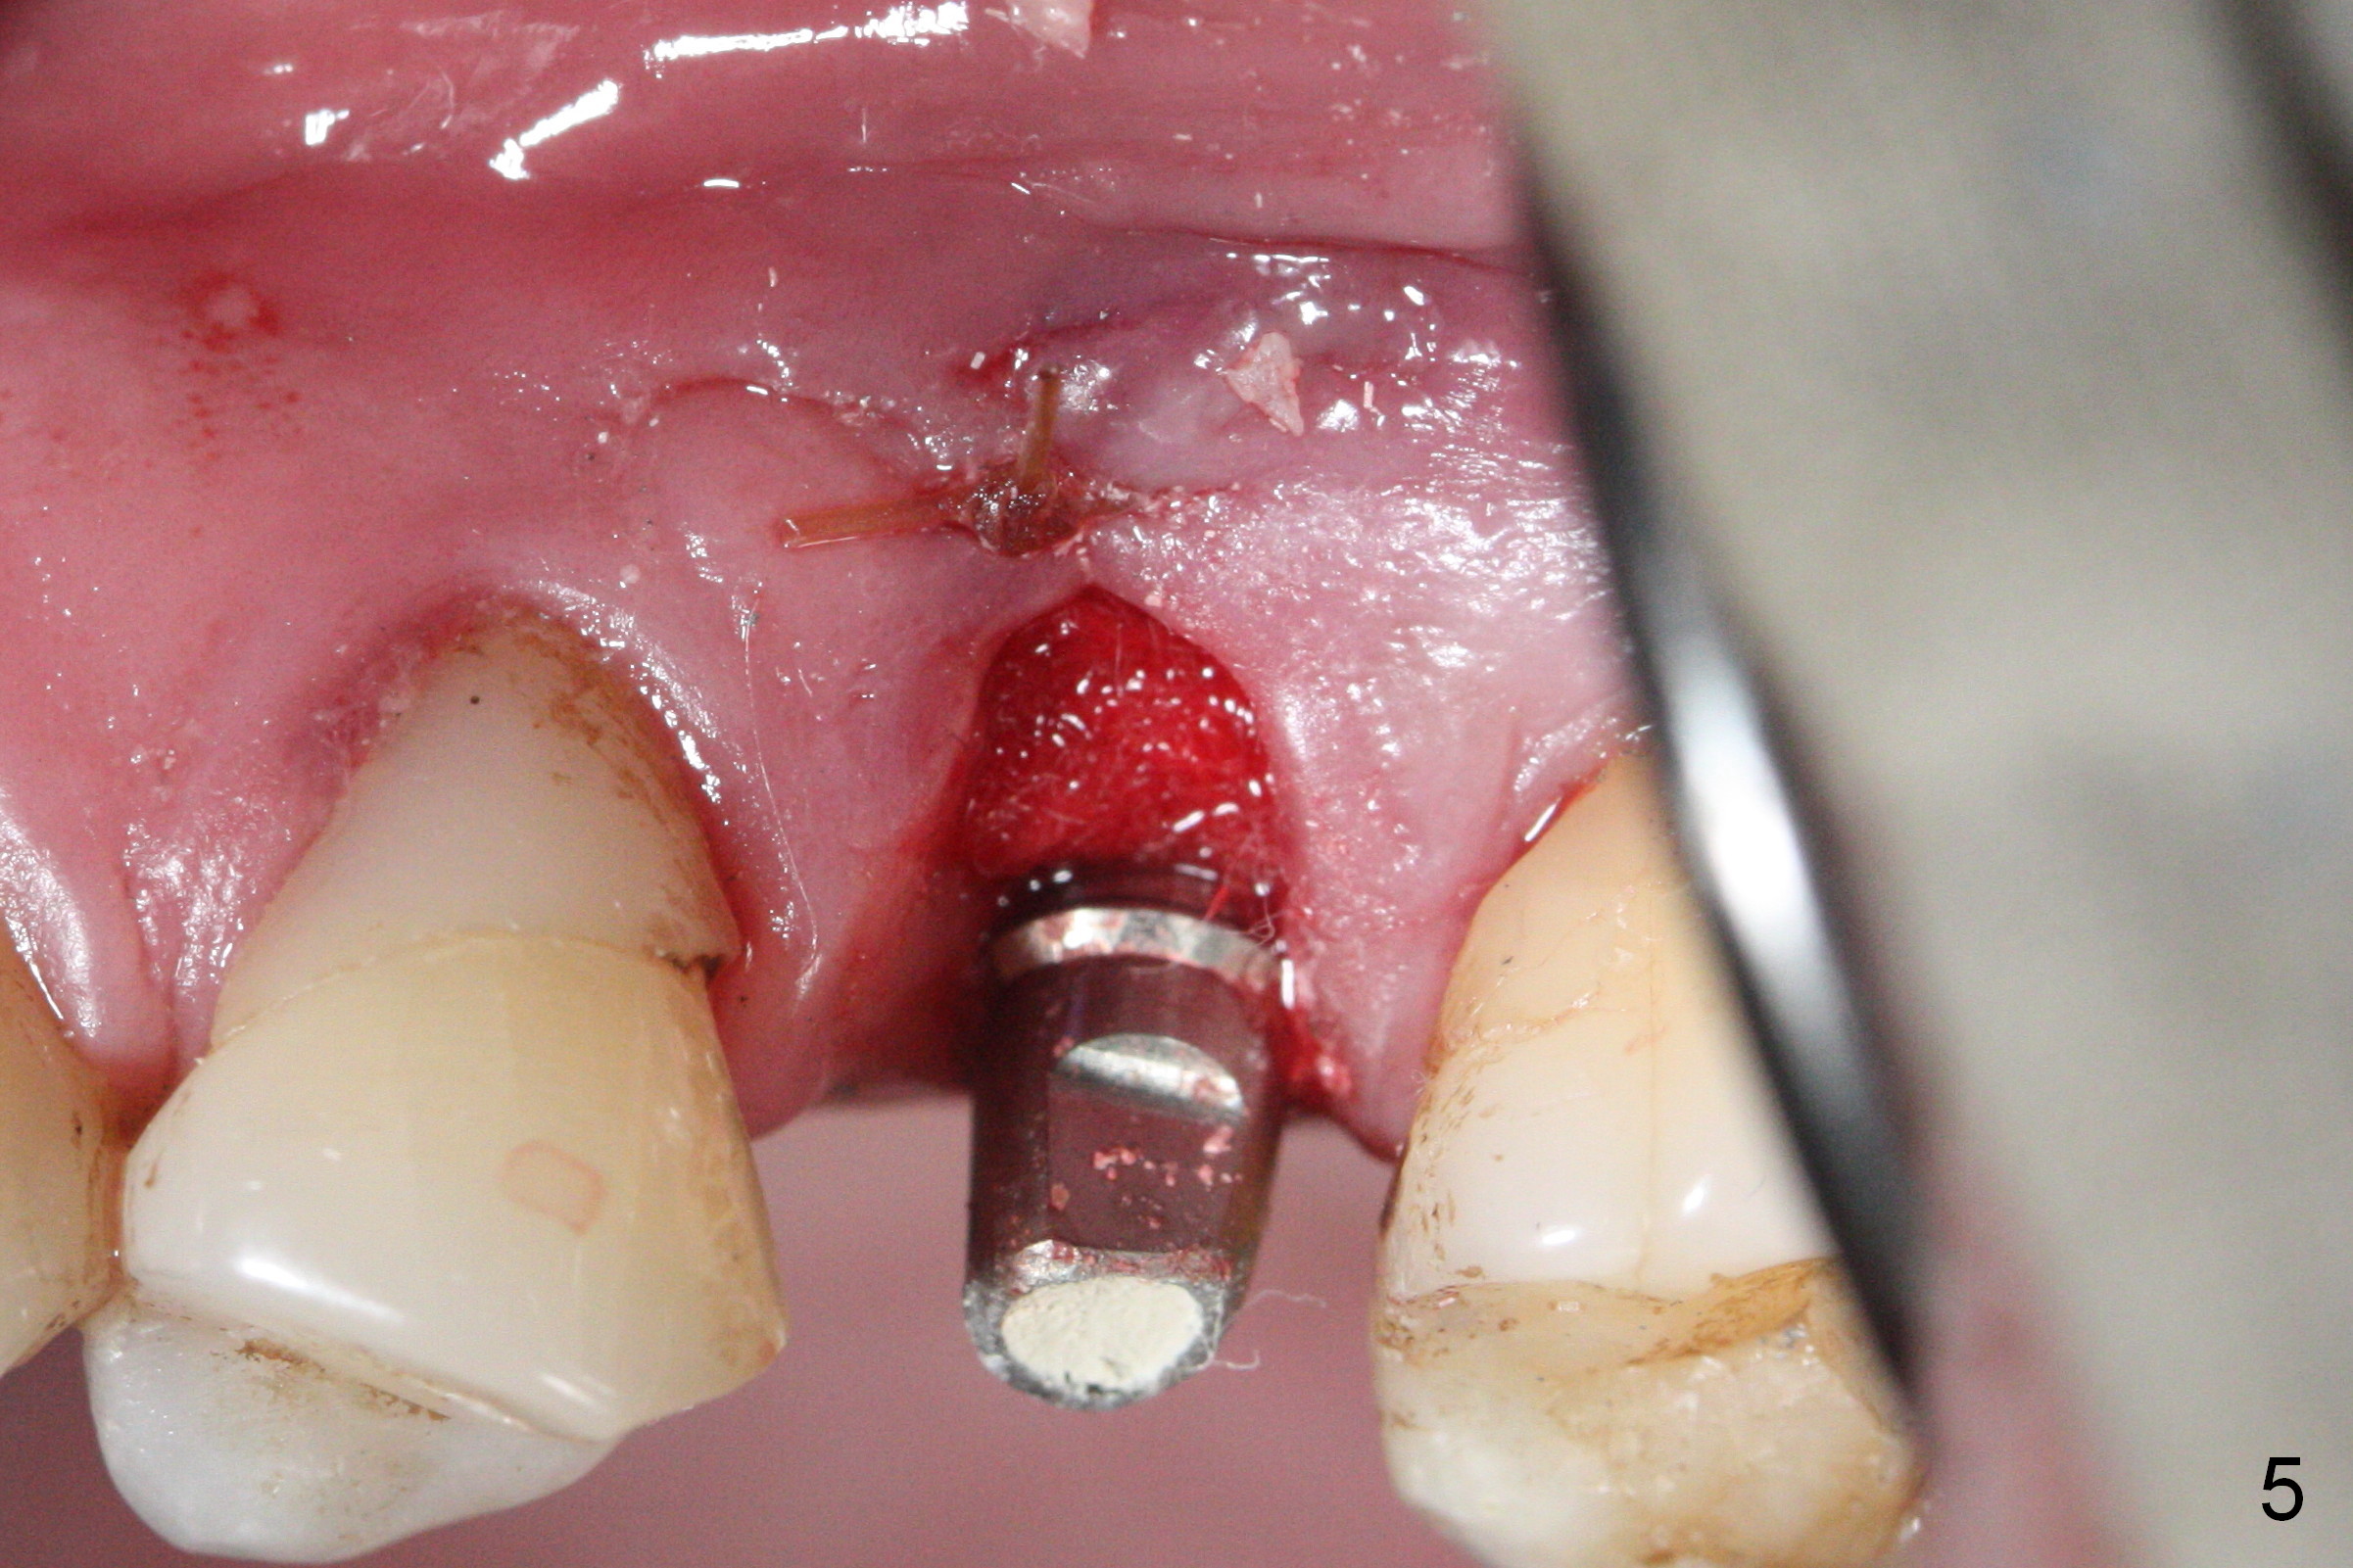

When the fractured root from the smoke-reducing patient is being removed by a root tip pick, the buccal gingiva is lacerated, partially due to loss of the buccal plate.  Later suturing is required (Fig.5).

Initial osteotomy depth is 18 mm (Fig.1 green line) with 9 mm in the native bone (red line).  The bone density feels to be low.  There is at least 2 more mm bone apically (pink line).  The depth is increased by 2 mm so that when a 3.8x15 mm implant is placed, there is 10-11 mm implant/bone contact (Fig.2 red line).  There is large bony defect (Fig.3 *), which is bone grafted (Fig.4 *).  Finally a longer abutment is placed (4.5x5.5(5) in Fig.4 vs. 4.5x4(5) in Fig.2,3).  The 5 mm cuff does not look too long buccally (Fig.5) or palatally (Fig.6).   To prevent postop buccal gingival overgrowth (2), the buccal margin of an immediate provisional is subgingival (Fig.7-9 *).  Bone density between #13 and 14 appears to increase 3 months postop (Fig.10).  The implant seems to be equi-crestal (Fig.11 ^).  There seems to be more bone growth (i.e., decreasing gap) 6 months postop (Fig.12).  Impression is taken.  A crown is delivered nearly 7 months postop (08/07/2017).   While there is minimal bone loss at #13 and 15 three years and 4 months post cementation, the tooth #14 and 18 are mobile (Fig.13,14).